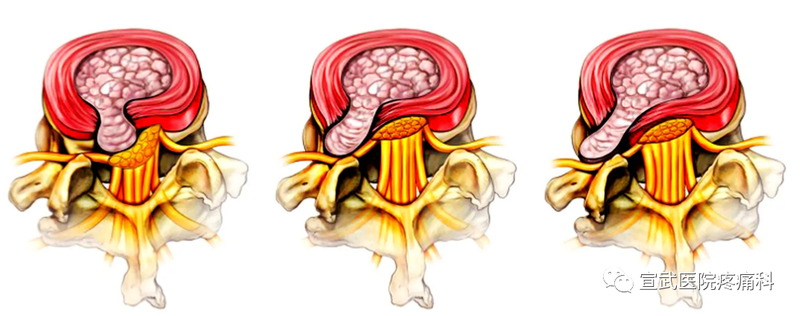

說起腰痛,很多人都經(jīng)歷過,但是都是怎樣治療的呢?貼膏藥,吃止疼片?今天我們先從一個(gè)腰痛患者的經(jīng)歷說起。門診最近來了一位三十歲的年輕媽媽,別看她年輕,她可是一位特別“突出”的老病人,這次不明原因又開始鬧腰痛了。在就診之前用她自己的話來說是:“翻身疼、坐立疼,走路時(shí)身體不能直立,身體向右側(cè)彎,打噴嚏和咳嗽會(huì)加重疼痛,穿鞋、刷牙、洗臉受限,彎不下腰”,為明確病因做了腰椎核磁共振檢查。這么一看是挺“突出”的啊,但這個(gè)病人僅表現(xiàn)為腰痛,明顯影像與癥狀不成正比!這是為什么呢?眾所周知,椎間盤突出癥是一種慢性疼痛性疾病,癥狀主要由椎間盤對(duì)相應(yīng)神經(jīng)的直接壓迫而產(chǎn)生的,因此分為頸椎、胸椎、腰椎間盤突出癥。一般通過臨床癥狀和影像學(xué)檢查確診,治療的根本原則是解除椎間盤對(duì)相應(yīng)神經(jīng)的壓迫。但有一種椎間盤突出是不容易看到的,那便是盤源性疼痛綜合征,這一類疾病是以椎間盤嚴(yán)重退行性改變?yōu)橹饕∫蛞鹋R床癥狀的疾病。該病的癥狀多變且詭異,疼痛往往不按照神經(jīng)分布而發(fā)生其中最常見的癥狀是腰腿痛,其次便是頸肩痛。隨著科技的進(jìn)步和生活壓力的增加,這一類疾病在臨床診療中逐漸增多和年輕化,同時(shí)由于盤源性疼痛綜合征的診斷相對(duì)困難,經(jīng)常發(fā)生誤診和漏診,臨床中很多反復(fù)不愈的腰肌勞損、坐骨神經(jīng)痛、肩周炎、腕管綜合征其實(shí)都是椎間盤退變搞的鬼??赐晟厦娴膬?nèi)容后您是不是又有新的疑惑?什么是椎間盤退變啊?它怎么就退變了?其實(shí)這個(gè)問題很好解答:我經(jīng)常拿椎間盤比作“餡餅”,中間的“餡兒”就是椎間盤的髓核,外面的“皮兒”就是就是椎間盤的纖維環(huán)。正常情況下這個(gè)“餡餅”的“皮兒”是非常致密的,它包裹的“餡兒”不會(huì)輕易的“漏”出來的。但是隨著年齡的增長和椎間盤壓力的增加,椎間盤會(huì)不同程度的發(fā)生退變。主要表現(xiàn)為“餡兒”失水,“皮兒”老化破裂,而漏出的這個(gè)“餡兒”又是刺激性較強(qiáng)的物質(zhì),刺激周圍產(chǎn)生炎性物質(zhì)和血管異常增生,而這部分異常增生的血管團(tuán)在核磁上變現(xiàn)為椎間盤高信號(hào)區(qū)(High-intensityzone,HIZ),它們通過刺激神經(jīng)根而引發(fā)疼痛。簡而言之就是“餡餅”變老、變干,出現(xiàn)裂縫,造成疼痛。而這一類型的疼痛通常影像學(xué)表現(xiàn)并不嚴(yán)重,呈現(xiàn)影像與癥狀不成正比的情況,因此盤源性疼痛又被稱為“看不見的椎間盤突出癥”。明白了上面的內(nèi)容,那我們?cè)僬J(rèn)識(shí)一下退變,直接上圖大家可能理解得更容易一些。正如這張腰椎核磁共振影像所示,藍(lán)色框中的椎間盤為正常椎間盤,呈中間“亮”,四周“暗”的表現(xiàn),其中亮的部分為健康的髓核組織,也就是我剛才說的“餡兒”,髓核中水的比重大,因此呈現(xiàn)發(fā)亮狀。而紅色框中的椎間盤變明顯變“黑”,臨床中成為“黑盤征”,是椎間盤退變的一種表現(xiàn),代表髓核失去了水分,因此核磁共振檢查中呈現(xiàn)暗黑色。這張圖中顯示的是纖維環(huán)(也就是“皮兒”)破裂后沿著裂口異常增生的血管團(tuán)。這些血管團(tuán)在核磁上表現(xiàn)為椎間盤高信號(hào)區(qū)(High-intensityzone,簡稱:HIZ)?,F(xiàn)在我們?cè)賮砜匆幌逻@位年輕患者的核磁影像圖片,您能發(fā)現(xiàn)問題了嗎?那么這位患者癥狀這么重,我們是如何治療的呢?首先患者的椎間盤屬于中心型突出,對(duì)神經(jīng)根的壓迫較輕,不易表現(xiàn)出神經(jīng)反射癥狀,即腿疼。其次HIZ局部的壓力增高,刺激局部小交感神經(jīng)產(chǎn)生疼痛信號(hào),引發(fā)疼痛,進(jìn)一步增加炎癥因子和致痛物質(zhì)的釋放。周而復(fù)始。若無法有效打破惡性循環(huán),病癥可能朝著惡化嚴(yán)重的方向一去不返。最后患者表示疼痛部位很深,經(jīng)詳細(xì)查體后發(fā)現(xiàn)患者的腰肌基本正常,沒發(fā)現(xiàn)明顯的疼痛點(diǎn),屈伸運(yùn)動(dòng)也屬大致正常范圍。在充分和患者交代病因及各種治療方法后,最終我們決定采用超聲引導(dǎo)下微創(chuàng)注射治療,針對(duì)該患者的病情及癥狀共治療了三次,并收到了非常滿意的治療效果。最后再說一下如何預(yù)防?防大于治,是疾病治療的根本。椎間盤退變是無法避免的,但我們可以通過適當(dāng)?shù)氖侄螠p緩?fù)俗儯苊馔俗冃纬杀P源性疼痛,大部分平時(shí)注意保養(yǎng)的朋友,都可以平穩(wěn)地度過這一時(shí)期,因此疾病不可怕,預(yù)防才是關(guān)鍵!1.避免勞累:現(xiàn)代生活節(jié)奏加快,壓力增大導(dǎo)致高危人群長時(shí)間保持不良體位是頸椎、腰椎間盤退變的重要原因,充分休息避免勞累是預(yù)防該疾病的重中之重。每小時(shí)放松頸部,勤抬頭,少低頭,平時(shí)盡量挺直腰背,不駝背,不哈腰,是預(yù)防疾病的原則。日常生活中要注意合理安排時(shí)間,避免給頸椎和腰椎帶來壓力。2.不睡高枕:俗話講高枕無憂,但對(duì)于該疾病的預(yù)防,這句話是不對(duì)的。高枕會(huì)在一定程度上的改變頸椎生理曲度,對(duì)頸椎是一種損傷。選擇合適的枕頭是使頸部充分休息的先決條件。建議選擇符合頸椎生理曲度的枕頭。3.腰部支撐:軟床,沙發(fā)等都是不建議使用的。在休息時(shí)建議對(duì)腰部進(jìn)行支撐,最簡單的辦法就是在腰后部墊一薄枕,維持腰部的正常生理曲度。4.鍛煉肌肉:在充分休息的前提下,適當(dāng)鍛煉頸部和腰部肌肉是非常有必要的,對(duì)頸椎和腰椎具有保護(hù)作用,頸椎操,頸椎抗阻運(yùn)動(dòng),小燕飛都是很好的鍛煉方式,適宜經(jīng)常鍛煉。5.適當(dāng)按摩理療:定時(shí)進(jìn)行頸椎按摩理療對(duì)疾病的預(yù)防有很大益處,按摩理療有助于頸部肌肉的血液循環(huán),減少炎癥物質(zhì)的堆積。但一定要切記避免暴力按摩。按摩理療一定要選擇正規(guī)的機(jī)構(gòu)和儀器,否則將適得其反,損害自身健康。6.保暖:保暖在預(yù)防中尤其重要,寒冷是疾病進(jìn)展和加重的因素,在寒冷天氣中為頸椎增加保暖措施會(huì)達(dá)到事半功倍的效果。